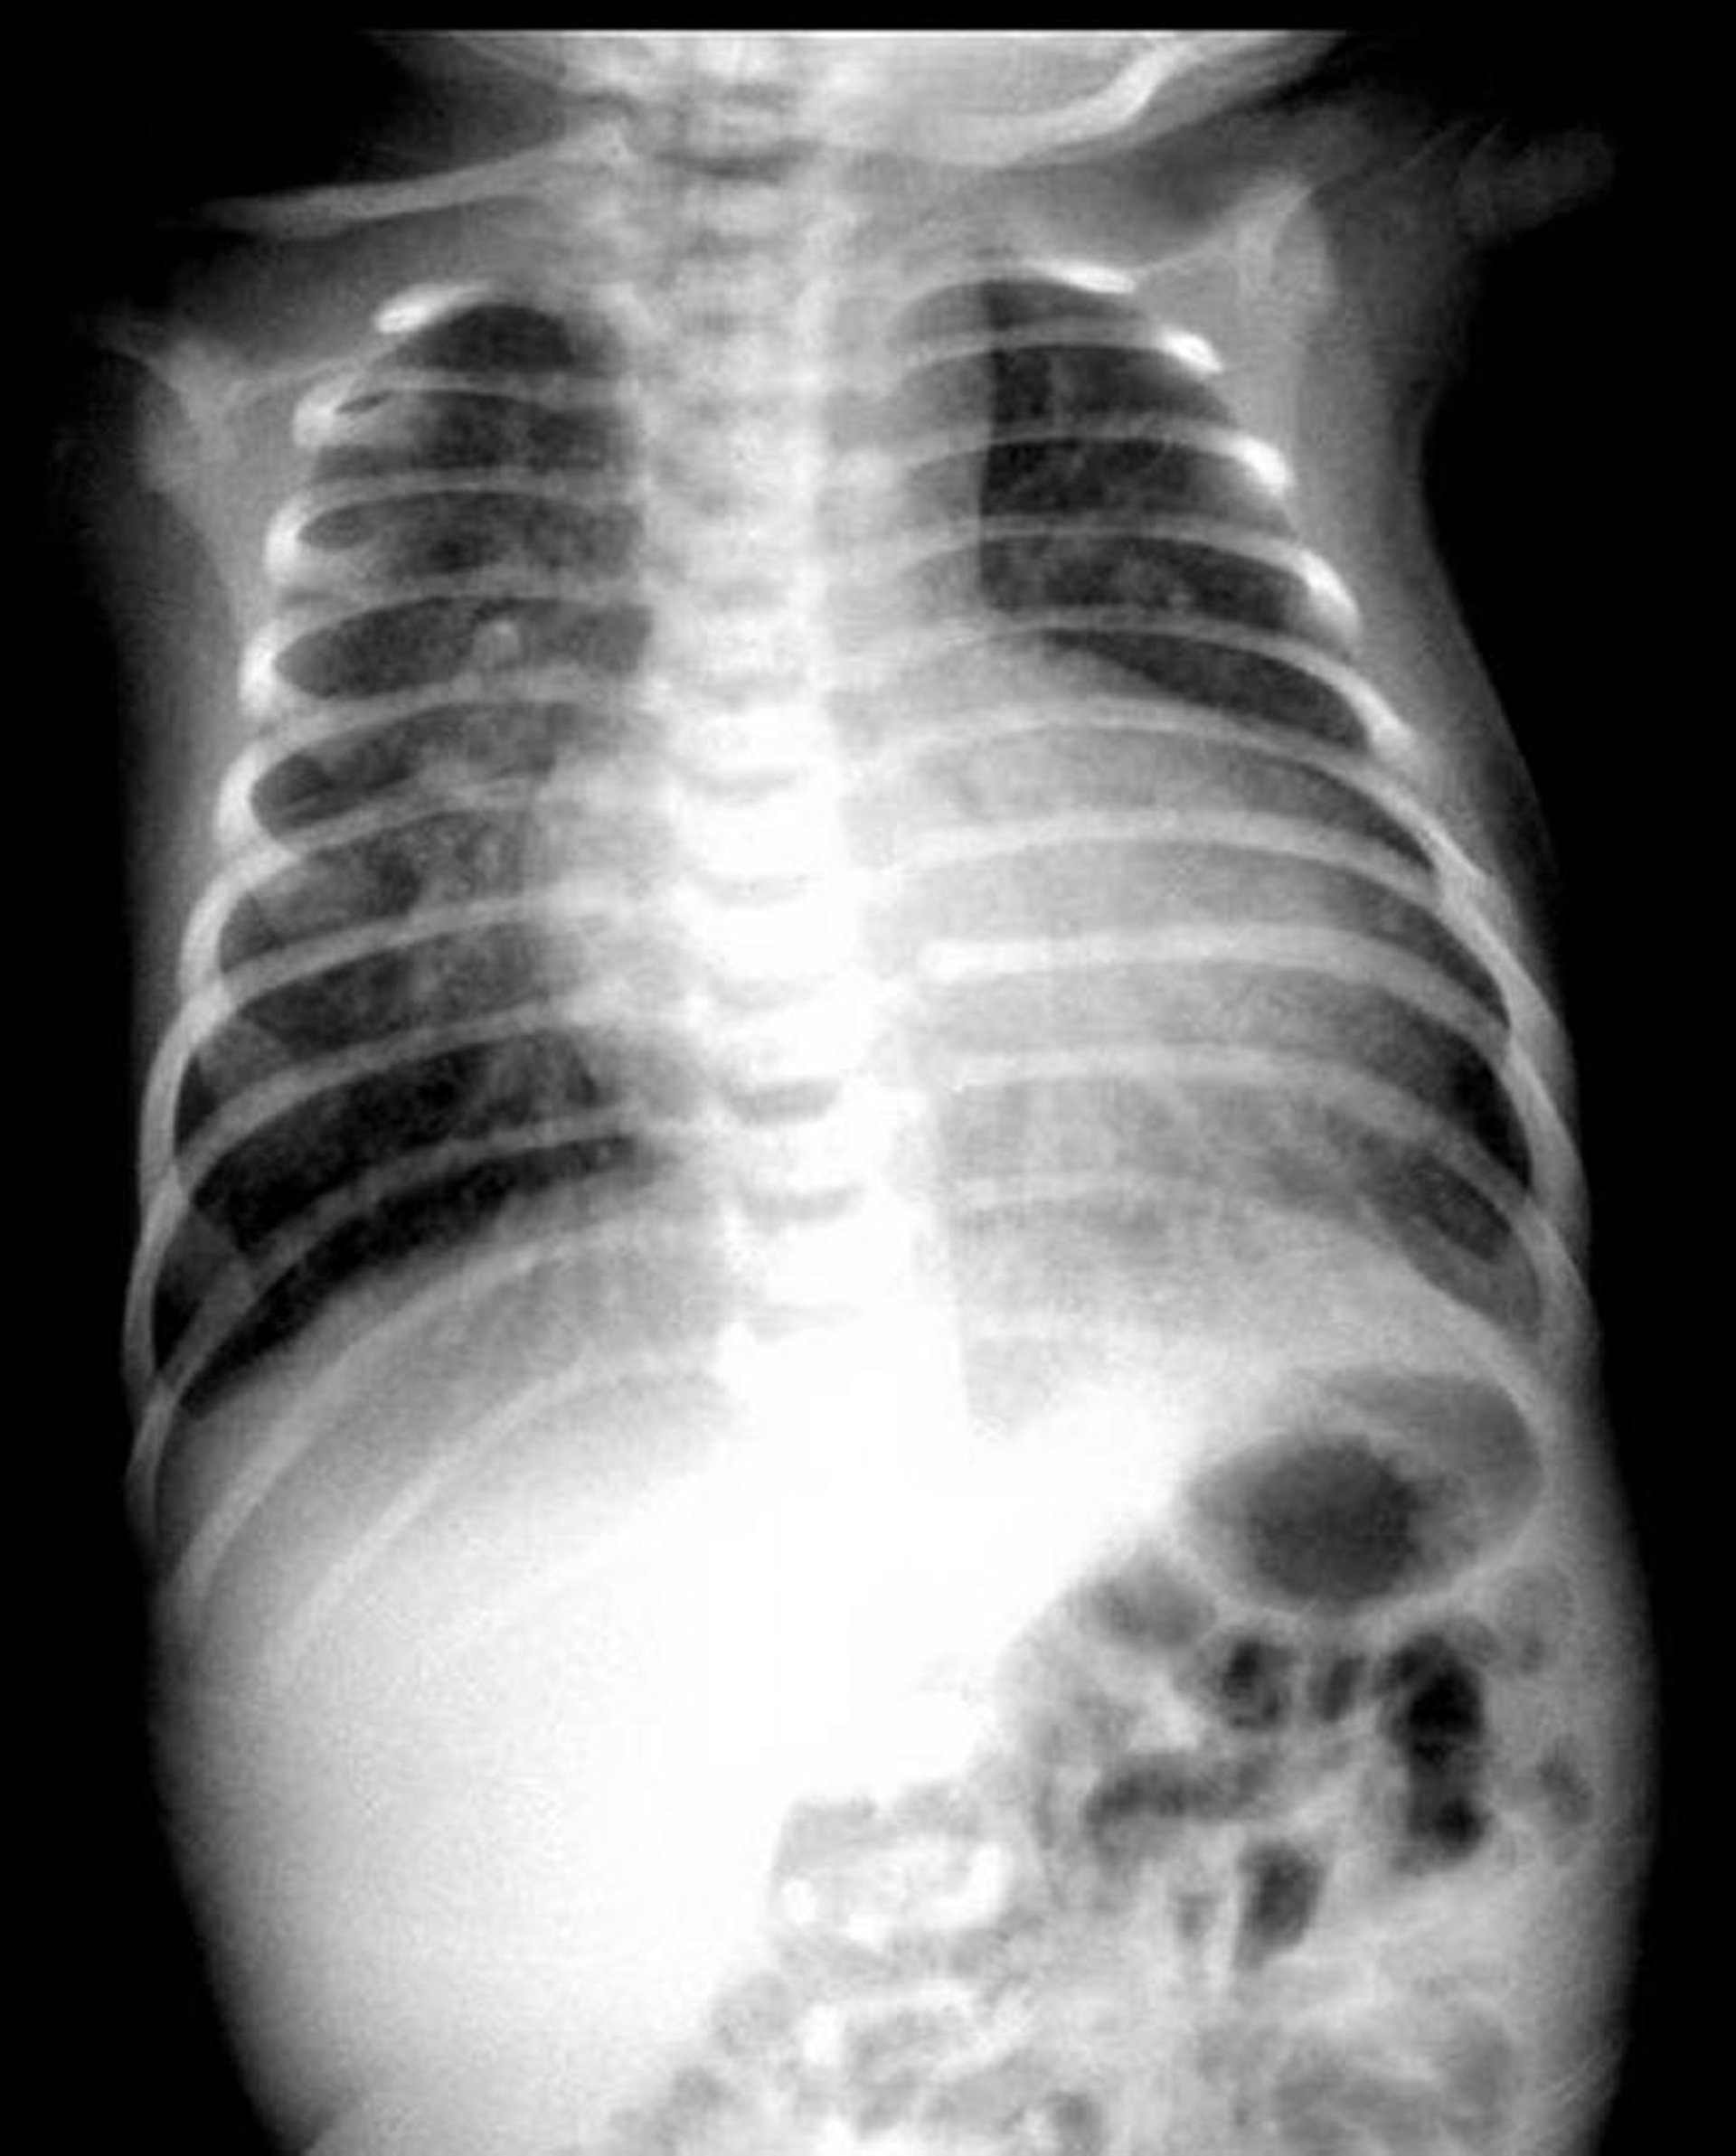

Röntgenaufnahme des Brustkorbs mit klassischem "Ei am Faden"-Erscheinungsbild bei einem Patienten mit Transposition der großen Arterien.

Abbildung zur Verfügung gestellt von Marie Baffa, MD.